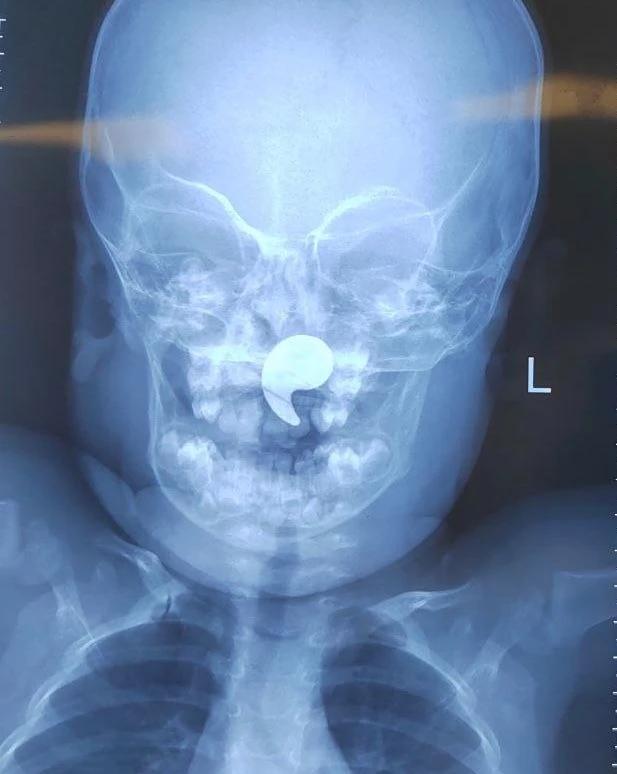

В Воронеже медики удалили магнит из носоглотки полуторагодовалой девочки, который она случайно проглотила.

Как выяснилось, малышка играла с магнитным элементом в форме запятой и проглотила его. Мать попыталась извлечь предмет пальцем, но нечаянно протолкнула его глубже — в носоглотку.

Девочку госпитализировали в оториноларингологическое отделение областной детской больницы №1. Там под общей анестезией врач с помощью эндоскопа успешно извлекла инородное тело.

В медучреждении отметили, что дети часто помещают в нос мелкие предметы, но магнит представляет особую опасность. Он мог переместиться в гортань или трахею, создав прямую угрозу для жизни.